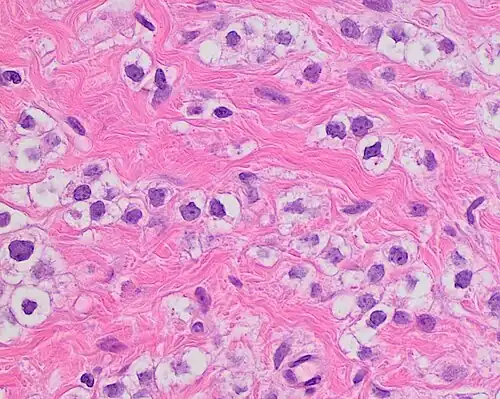

Nuclear pleomorphism

This parameter assesses whether the cell nuclei are uniform like those in normal breast duct epithelial cells, or whether they are larger, darker, or irregular (pleomorphic). In cancer, the mechanisms that control genes and chromosomes in the nucleus break down, and irregular nuclei and pleomorphic changes are signs of abnormal cell reproduction.

Note: The cancer areas having cells with the greatest cellular abnormalities should be evaluated.

- 1 point: nuclei with minimal or mild variation in size and shape

- 2 points: nuclei with moderate variation in size and shape

- 3 points: nuclei with marked variation in size and shape

-

Ductal carcinoma with mild nuclear pleomorphism. -

Invasive ductal carcinoma with moderate nuclear pleomorphism. -

Invasive lobular carcinoma with moderate nuclear pleomorphism. -

Invasive ductal carcinoma with marked nuclear pleomorphism.